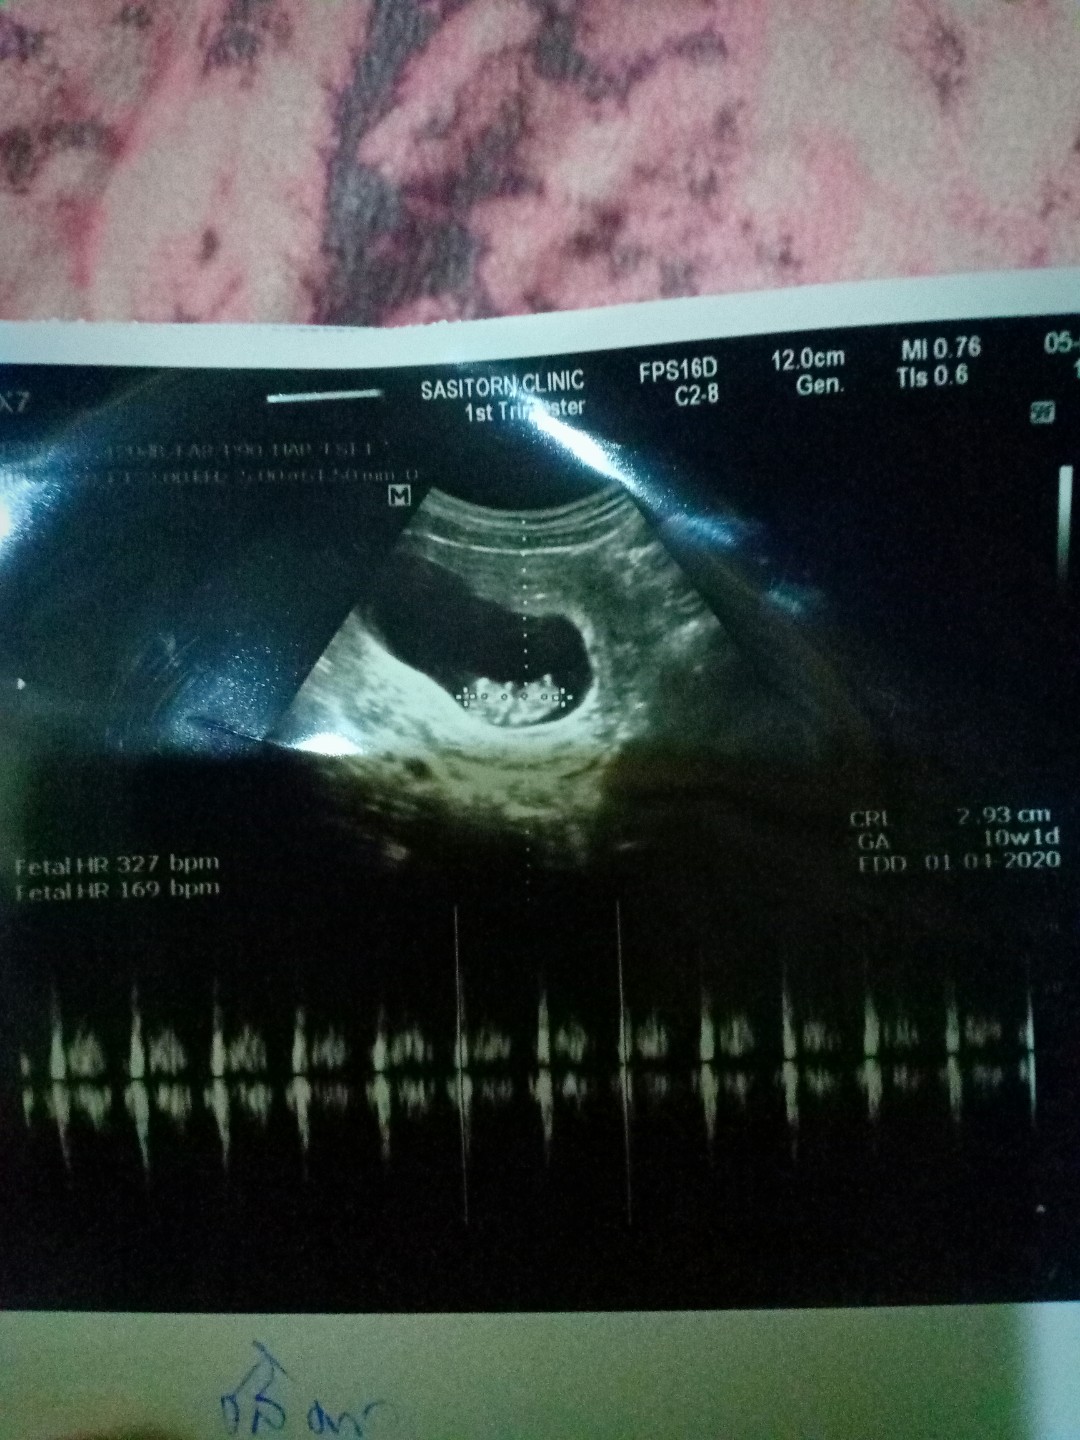

10wตอนนี้36wแล้วค่ะ